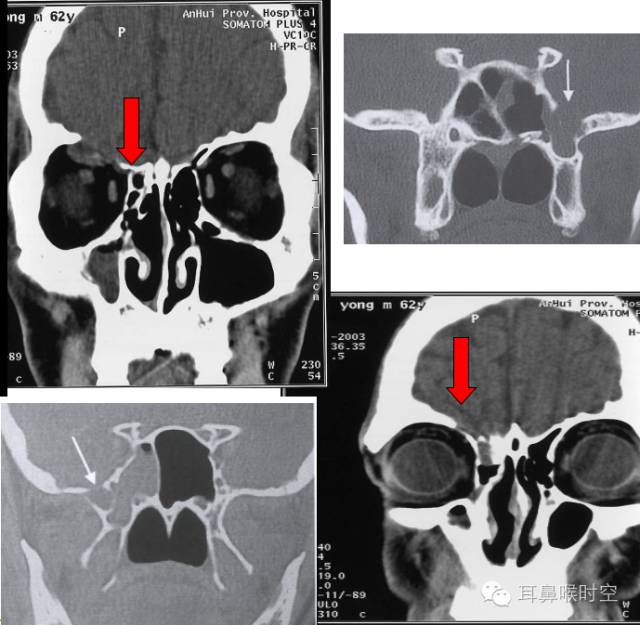

自发性脑脊液鼻漏

左:筛顶漏伴有鼻息肉 右:筛板漏

脑膜眶膨出与筛顶缺损

垂体瘤术后蝶窦漏

外伤性脑脊液漏